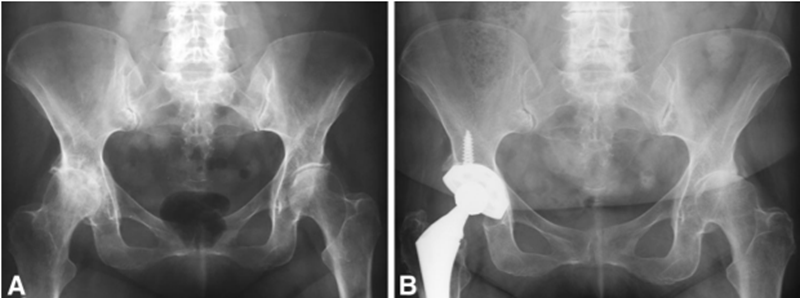

图 3A-B 这些前后 AP位 骨盆 X 线片显示了一名典型的左髋发育不良的研究患者。 (A) 本片是研究纳入时右髋的术前 X 线片,此时患者左髋定义为 Tönnis 0 退行性改变。 (B) 这张随后的 X 线片是在 18 年后拍摄的,此时左髋出现了 Tönnis 3 级退行性改变。